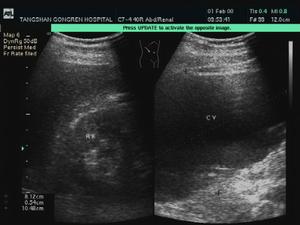

(8)B型超音波以經直腸B超較好,可見囊性結構,呈無回聲特徵,並可了解囊腫大小,易與實質性腫塊鑑別。可分辨出病變與前列腺、精囊的關係,經腹B超可了解同側腎、輸尿管是否缺如或發育不良。

精囊解剖直腸指檢在前列腺側上方精囊區可捫及囊性腫物,較大時雙合診陽性,按壓囊腫有時可獲分泌物。型超音波以經直腸B超較好,可視囊性製作,呈無回聲風味,並可得知囊腫大小,易與實質性腫塊鑑別。可判明出病變與前列腺、精囊的關係,經腹B超可真切同側腎、輸尿管是否缺如或發育不良。